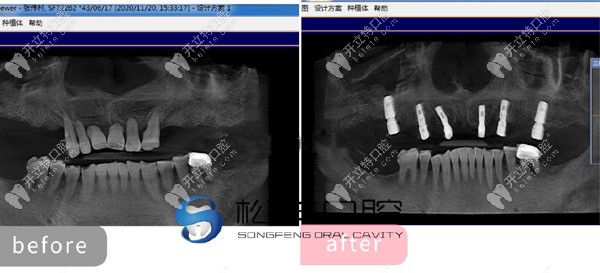

★ 上半口做了6顆即刻負(fù)重種植牙的CT片

上半口做了6顆即刻負(fù)重種植牙的CT片

通過這些真人的種植圖,可以看出。上海松豐口腔的種植技術(shù)真的不是吹的!但有人還質(zhì)疑上海松豐齒科正規(guī)嗎,這我可得來說道說道了!